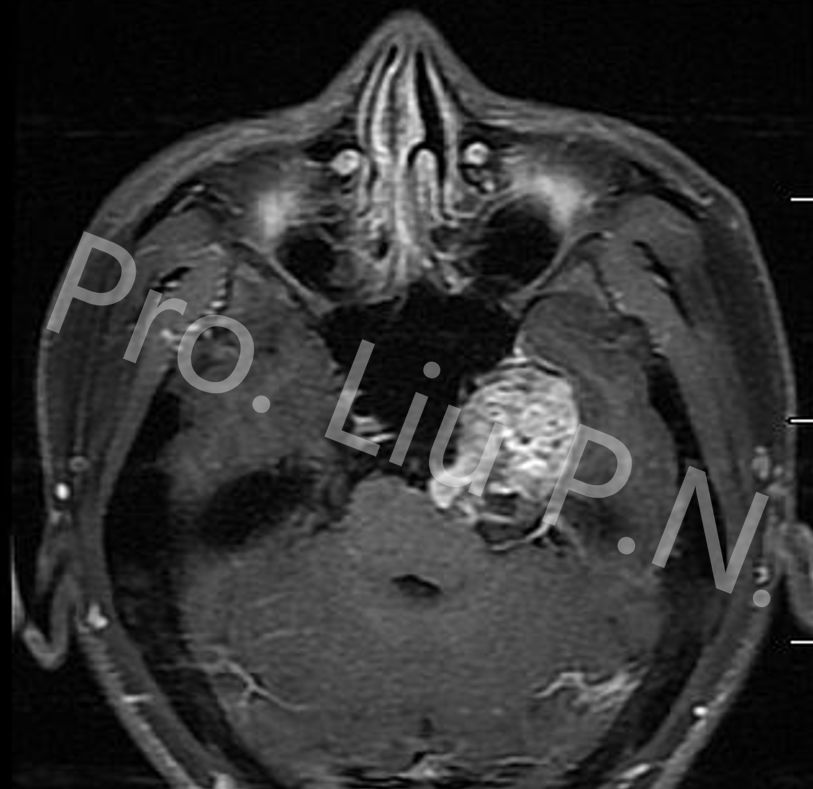

十二、经上颌窦-蝶骨大翼-海绵窦入路手术案例

--下颌神经起源神经鞘瘤

![]()